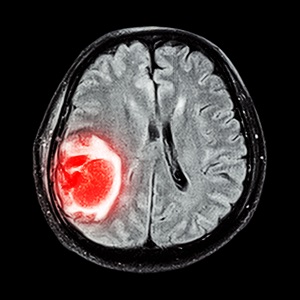

- МРТ